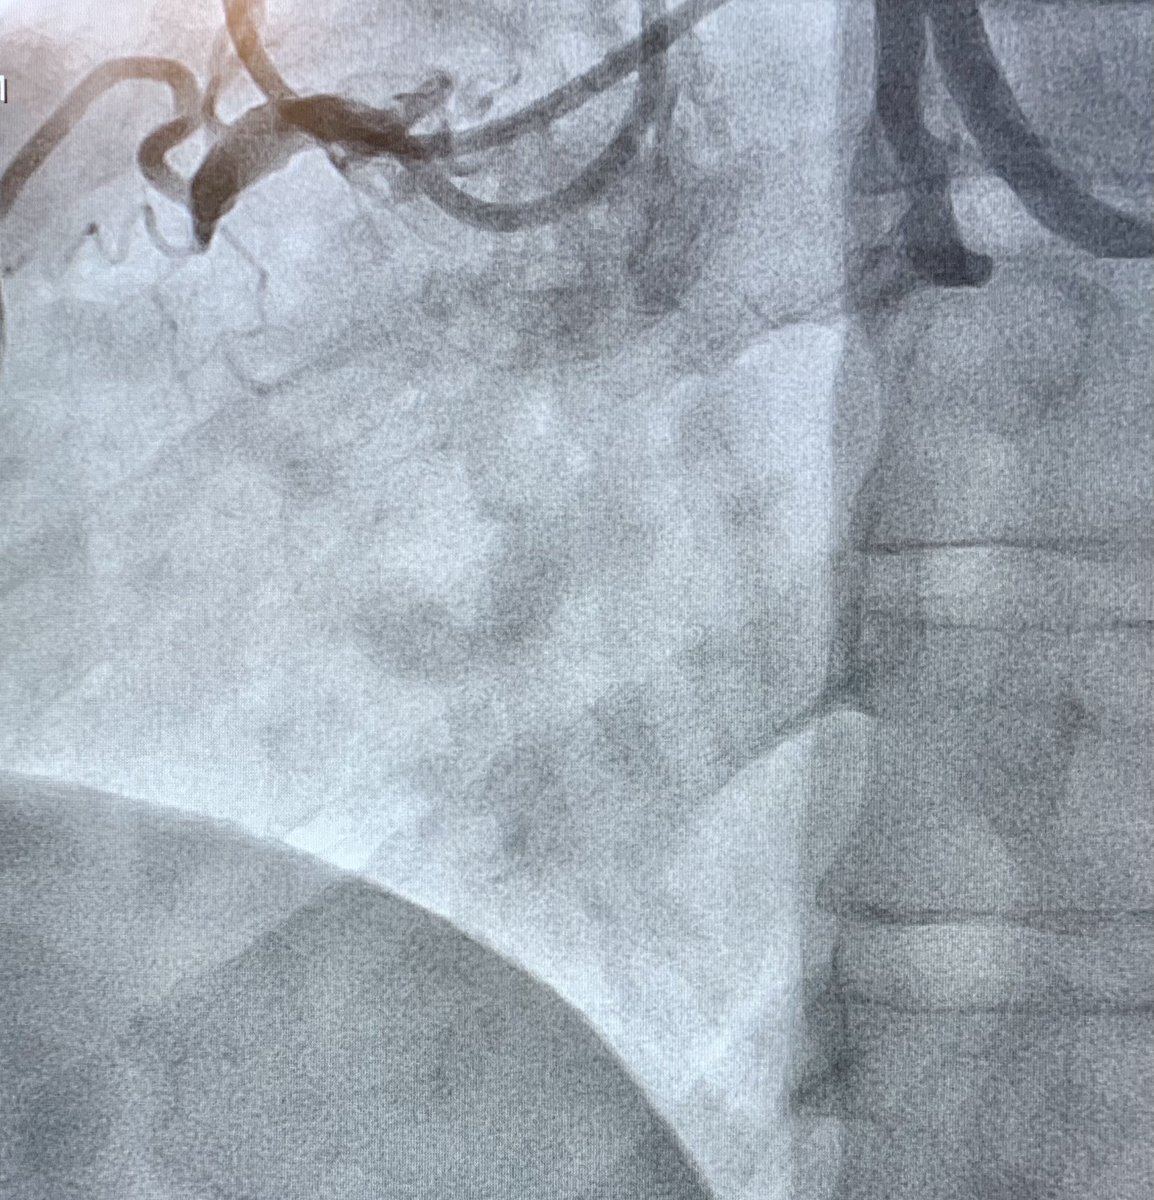

Tale of 2 CTOs: dual simultaneous coronary injections, wire escalation, and antegrade dissection re-entry for successful revascularization. #hybridalgorithm @jcgeorgemd @GPAngioClub @ACVCPhila @PennCardiology @PennCVFellows

Another successful #CTOPCI using Crossboss and wire escalation for #ADR topped off with #IVL for a calcified blunt cap with excellent results. #PennsyInterventions @jcgeorgemd @GPAngioClub @ACVCPhila @PennCardiology @PennCVFellows @BSCCardiology @ShockwaveIVL

I would fix the RCA first then stage the LAD. Since the LAD is a true CTO, bring the heavy artillery as @TheNarulaSeries says. 2 guides, be prepared for all aspects of the #hybridalgorithm. Nice case.